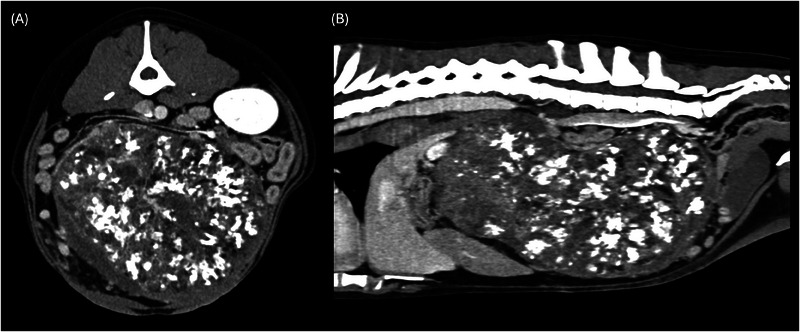

The aim of this retrospective multicentric case series is to describe the CT findings of ovarian neoplasia in dogs. Twenty dogs with pre- and postcontrast CT exams and cytological/histological diagnosis of ovarian neoplasia were included. Five dogs presented with bilateral tumors, for a total of 25 neoplasms: 15 carcinomas (4 bilateral), 4 granulosa cell tumors, 2 poorly differentiated malignant neoplasia (bilateral), 2 luteomas, 1 teratoma, 1 dysgerminoma. In two dogs, the tumor developed from an ovarian remnant. Ovarian tumors showed variable size, lobulated shape, and precontrast heterogenous appearance. Mineral foci and/or fat components were rare, observed in teratoma, granulosa cell tumors (2), and ovarian carcinoma. Tumor type was not found to be associated with any CT features. Larger masses were more likely located in the central abdomen ventral to the ipsilateral kidney, demonstrated signs of tumor rupture, and were associated with abdominal or sternal lymphadenopathy and peritoneal effusion. A tortuous ovarian artery was constantly detectable, associated with an enlarged gonadal vein (12 cases). Related cavitary changes were peritoneal effusion (14 dogs) and sternal lymphadenopathy (7 dogs). Presumed or confirmed metastasis was reported in 9 of 20 cases, with CT evidence of transcoelomic (serosal thickening, peritoneal nodules, omental cake, implant lesions to the liver, spleen, and diaphragm), lymphatic and hematogenous spread (lungs, liver, bone, muscles, and spleen). In conclusion, the present study reports the CT features of different canine ovarian neoplasia. A tortuous ovarian artery may be useful to consistently recognize the ovarian origin of a large abdominal mass.